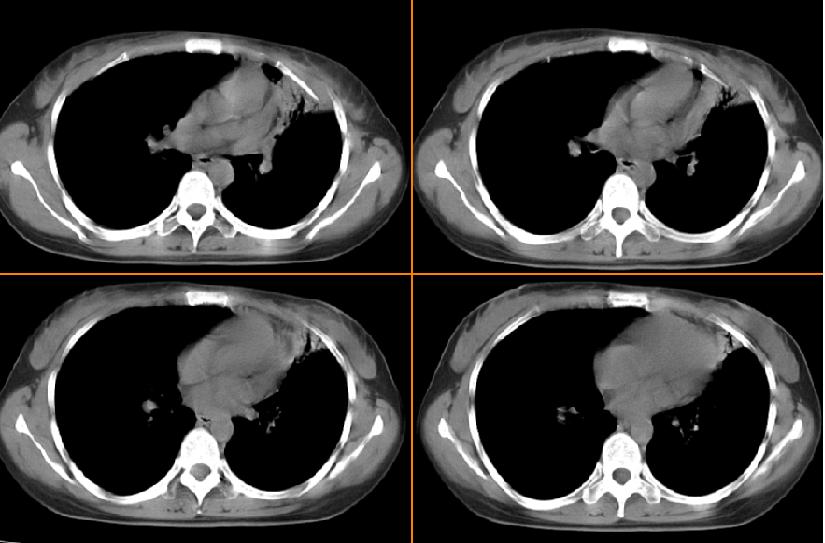

女,33岁,咳嗽5月。

左肺上叶前段致密,内见空气支气管征,相应部位胸膜增厚粘连,双肺上其他肺叶不同程度斑片状播散病灶,结合咳嗽5月的病史,考虑:双肺上叶继发性肺结核。

左肺上叶前段致密,内见空气支气管征,相应部位胸膜增厚粘连,双肺上其他肺叶不同程度斑片状播散病灶,结合咳嗽5月的病史,考虑:双肺上叶继发性肺结核伴左肺上叶肺含气不良。